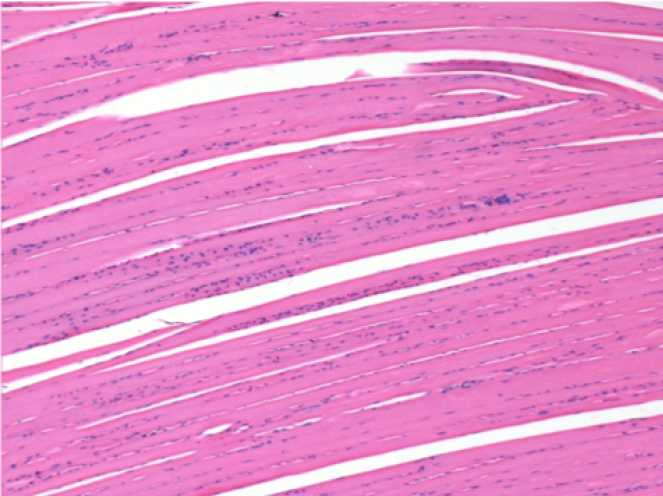

1 mes después de la inyección de Endopeel 0,1 ml en el músculo pretibial derecho.

¡Lo que se ve en negro en las imágenes no es una necrosis como podrían imaginar algunos científicos!

De hecho, hay que tener en cuenta 4 conclusiones

08